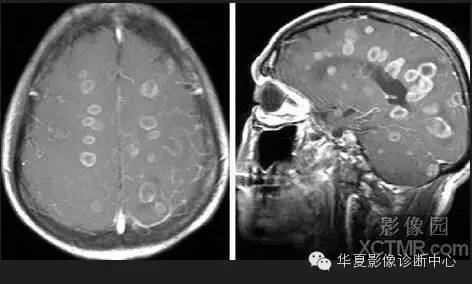

30.白靶黑靶征:

脑猪囊尾蚴病在CT平扫大多表现为小园形囊性病灶,大小为4~6mm,CT上为类圆形低密度内可见点状高密度,即所谓黑靶征。或在MRI上呈长T1长T2信号,部分病灶在T1WI上黑色的低信号内见到点状高信号,即黑靶征;在T2WI白色高信号内见到点状低信号,即白靶征。

脑囊尾蚴病,脑实质囊虫CT显示多发的圆形或卵圆形大小不一(0.1~0.5 cm)的结节状高密度影及(或)多个类圆形低度密度灶,边缘可见小点状高密度影,直径0.5~1.5 cm,部分病例病灶显示不清楚,仅见大片低密度区,类似脑炎改变。少数病例可见大囊型病灶,直径达7~8 cm,多为单发或仅有几个病灶。脑室内囊虫为圆形囊状,直径为1~4 cm,边缘光滑,稍低于脑脊液密度,或近似脑脊液密度。脑池、颅底部蛛网膜下腔囊虫呈葡萄状低密度病灶,囊壁有浅淡强化。可有脑积水表现。

脑囊尾蚴MR表现:脑实质囊虫:1)多发小囊型,系多个存活期囊尾蚴并存的表现。MR表现为双侧大脑皮质区有多个散在分布的小圆形或卵圆形小囊,直径0.3~0.8 cm,呈长T1WI、长T2WI信号,壁内可见偏心型小点状影,即囊虫头节,呈短T1WI、稍短T2WI信号改变,周围水肿不明显。Gd-DTPA增强扫描,囊壁呈环状强化,头节呈点状强化。2)大囊型,系一个巨大囊尾蚴或多个囊尾蚴融合而成的表现。MR表现为脑实质内巨大的圆形或卵圆形囊腔,其内无头节,信号与脑脊液一致,呈长T1WI、长T2WI信号,周围可合并脑水肿,有占位效应。Gd-DTPA增强扫描,大囊本身多无强化,若周围有纤维组织增生,可呈环状强化。脑室内囊虫亦引起脑积水,MRI表现为囊虫所在部位脑室呈不对称性增大,呈长T1WI、长T2WI信号,存活期囊虫多较脑实质型虫体体积大,直径可>2 cm,囊壁上可见偏心型头节影呈稍短T1WI、短T2WI信号。Gd-DTPA增强扫描,囊虫存活期囊壁无强化;退变死亡期囊壁可明显强化。脑池、颅底部蛛网膜下腔囊虫MRI表现为葡萄串样异常信号影,呈长T1WI、长T2WI信号,纤维间隔呈等T1WI、短T2WI信号,无囊虫头节。Gd-DTPA增强扫描,囊壁及间隔可轻度强化。 医学百科网 | YxBaike.Com